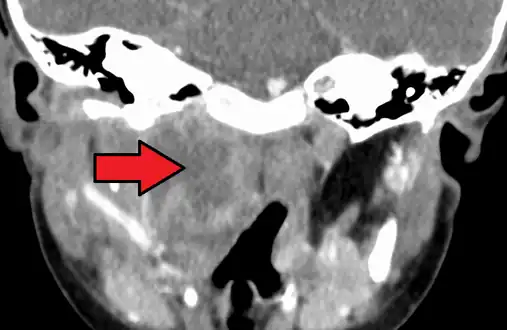

| A lateral cervical spine x-ray demonstrating prevertebral soft tissue swelling (marked by the arrow) as seen in a person with a retropharyngeal abscess | |

X-ray of the neck often (80% of the time) shows swelling of the retropharyngeal space in affected individuals. If the retropharyngeal space is more than half of the size of the C2 vertebra, it may indicate retropharyngeal abscess.[5]